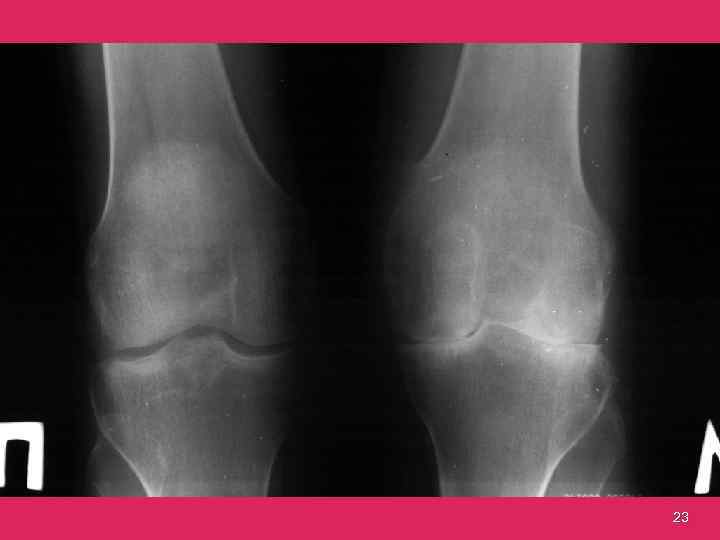

Критерии ЮРА основаны на критериях АРА, адаптированы для детей (А. В. Долгополова и соавт. , 1977) Б. Рентгенологические признаки: § Остеопороз, мелкокистозная перестройка костной структуры эпифизов § Сужение суставных щелей, костные эрозии, анкилоз суставов § Нарушение роста костей § Поражение шейного отдела позвоночника В. Лабораторные признаки: § Положительный ревматоидный фактор § Положительные данные биопсии синовиальной оболочки При наличии 8 признаков устанавливается диагноз «классический» ЮРА, 4 признаков – «определенный» и 3 признаков – «вероятный» ЮРА 18

Рентгенологические стадии ЮРА Стадии Рентгенологические признаки Ia Костные элементы суставов без изменений, отек периартикулярных мягких тканей Околосуставной остеопороз, иногда отсутствие деструктивных изменений Остеопороз, наличие незначительной деструкции хряща или подхрящевой ткани, сужение щели Остеороз, деструкция костного хряща (эрозия) Ib II IV Остеопроз, деструкция костного хряща, наличие подвывихов и анкилозов 19

§ § Определение рентгенологической стадии (по Штейнброккеру): I стадия: эпифизарный остеопороз II стадия: эпифизарный остеопороз, разволокнение хряща, сужение суставной щели, единичные эрозии III стадия: деструкция хряща и кости, формирование костно-хрящевых эрозий, подвывихи в суставах IV стадия: критерии III стадии в сочетании с фиброзным или костным анкилозом Определение степени активности болезни: – 0 степень: СОЭ до 12 мм/ч – I степень: СОЭ 13 -20 мм/ч – II степень: СОЭ 21 -39 мм/ч – III степень: СОЭ 40 мм/ч и более 21

Рентгендиагностика 22

23